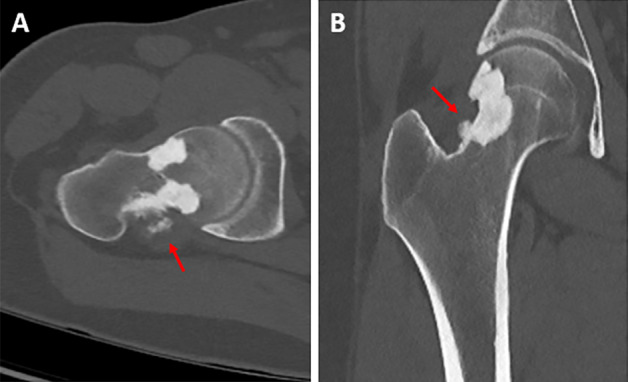

教学要点Melorheostosis 是一种罕见的硬化性骨发育不良,其特点是骨皮质周围和/或骨皮质内侧硬化,导致骨轮廓起伏增厚,类似于 "滴落的蜡烛蜡"。

Teaching point: Melorheostosis is a rare sclerosing bone dysplasia, characterized by sclerosis at the periosteal and/or endosteal side of the cortex, causing undulating thickening of the bony contour resembling "dripping candle wax."